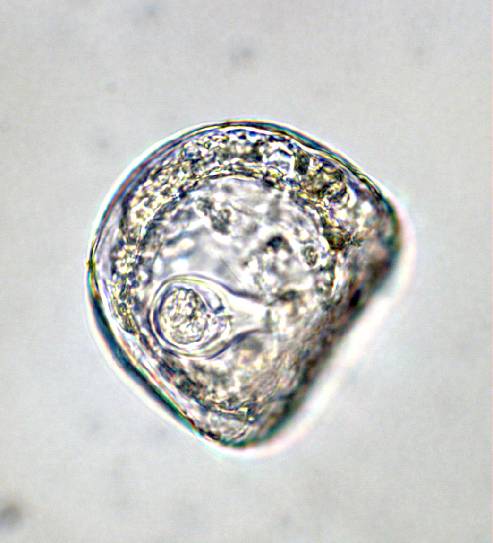

50 µm

Protozoa